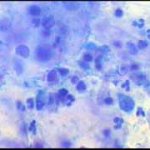

Ατυπα κύτταρα ενδοτραχήλου, αμεση χρώση με bleu de methylen 0,25% μεγεθ. 10Χ40. Αδενοκαρκίνωμα ενδοτραχήλου - ενδομητρίου

Ατυπα κύτταρα ενδοτραχήλου, αμεση χρώση με bleu de methylen 0,25% μεγεθ. 10Χ40. Αδενοκαρκίνωμα ενδοτραχήλου - ενδομητρίου